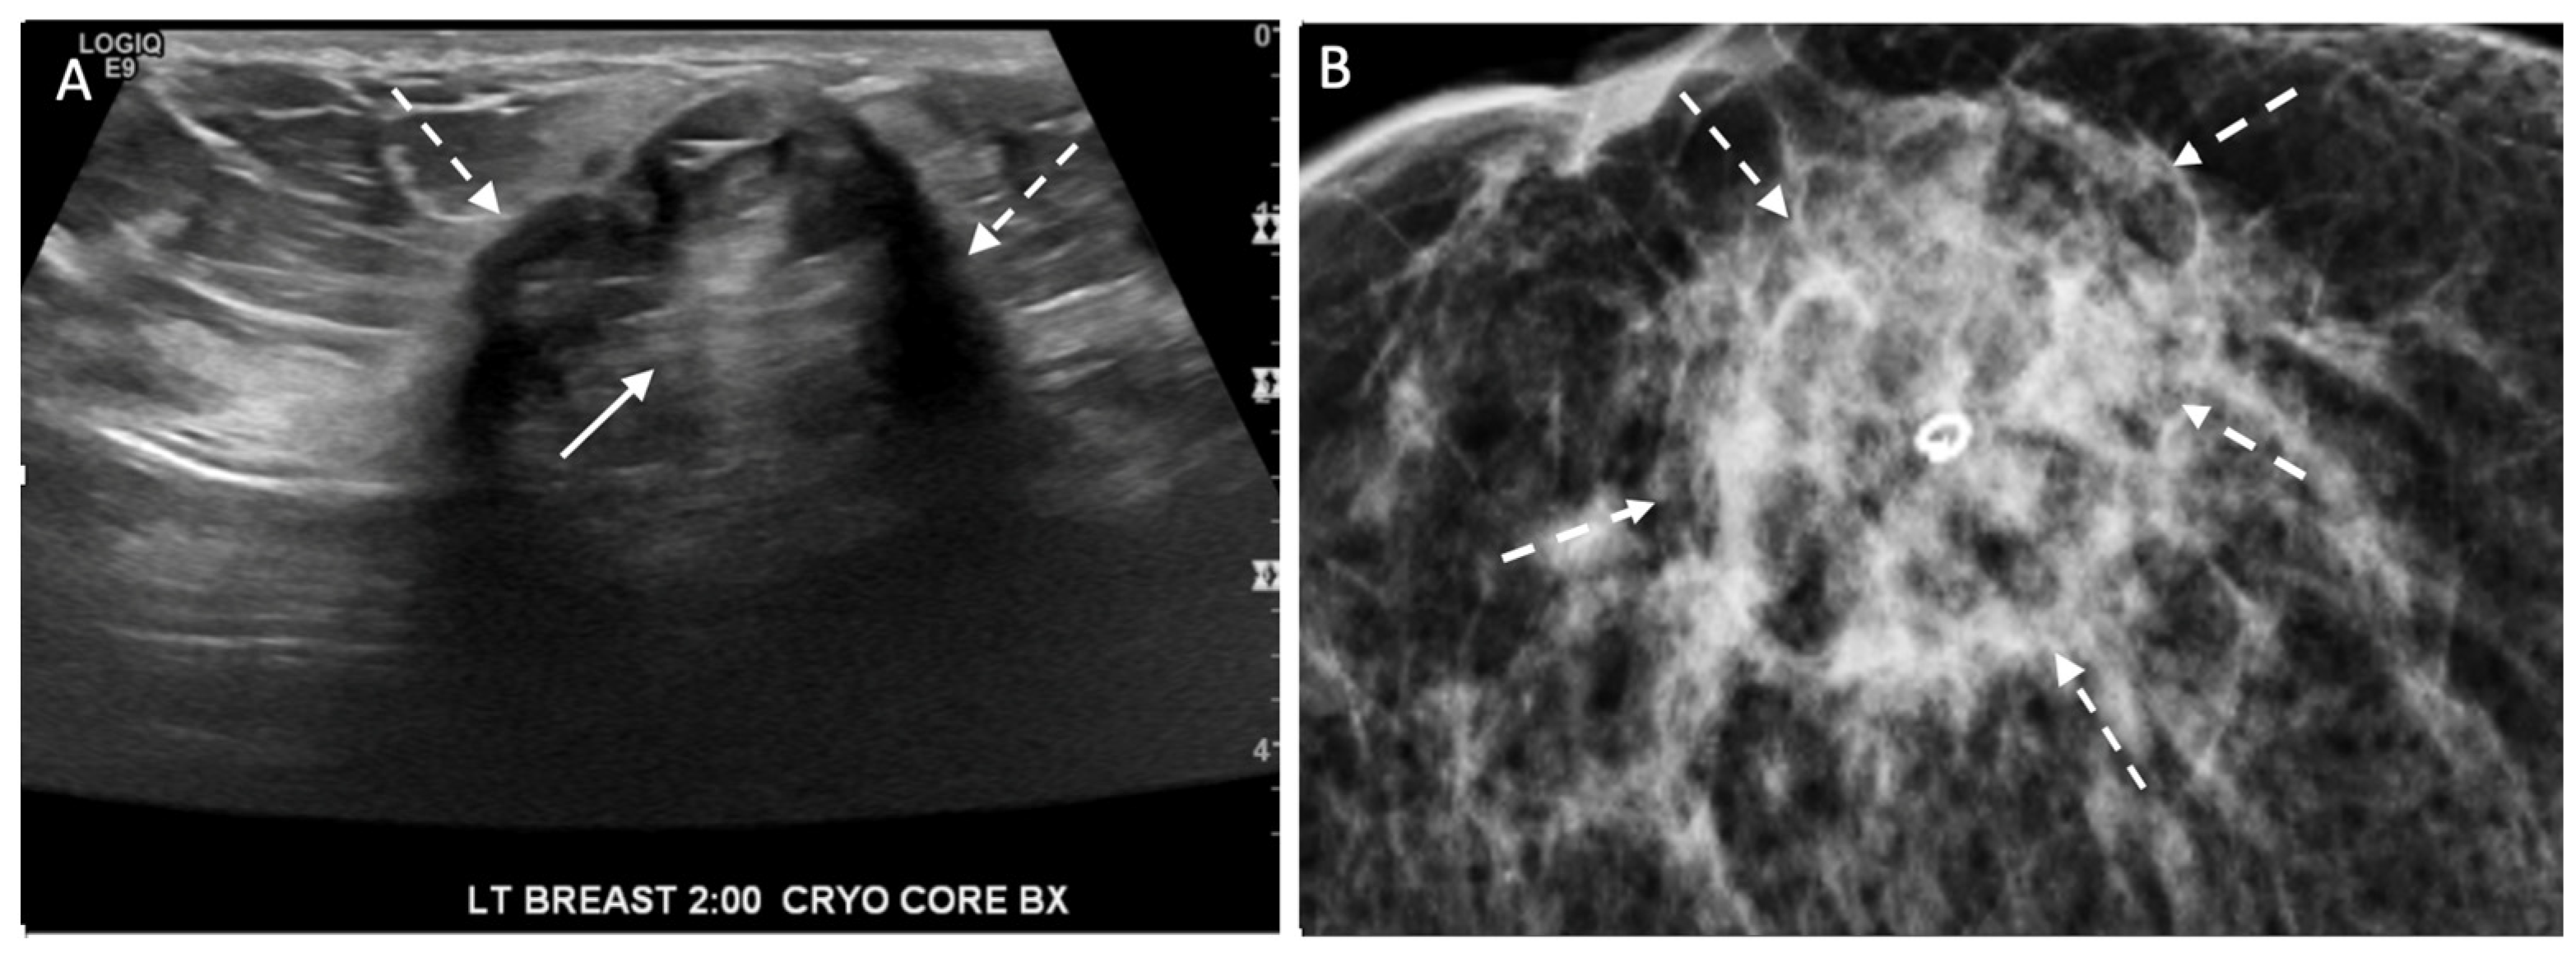

Digital Mammography. Breast cancer staging should include bilateral digital diagnostic mammograms (preferably 3D mammograms or tomosynthesis) to evaluate the extent of disease. Although cryoablation is generally performed under ultrasound or CT-scan guidance, high-quality mammography might reveal additional areas of cancer in the same region of the breast (multifocal cancer) or in a different region of the breast (multicentric cancer) that might impact patient selection or alter the cryoablation treatment plan. Multicentric and multifocal breast cancer is generally regarded as a contraindication to cryoablation. Pre-treatment assessment of the mammograms should seek the detection of spiculations (radial tumor extensions) and/or microcalcifications that might reach beyond the main tumor mass and require incorporation in the cryoablation treatment zone (Figure 1). Since mammography is the only imaging study that reliably shows microcalcifications, mammography plays a particularly important role in determining disease extent when suspicious microcalcifications are part of the disease process. Consequently, patients who are generally opposed to obtaining screening mammograms should be encouraged to have at least one set of pre-treatment diagnostic mammograms to exclude the presence of suspicious microcalcifications that could impact patient selection and/or treatment planning.

Figure 1.

Mammogram showing density corresponding to a palpable mass (see dashed lines) as well as suspicious microcalcifications (arrows) and inset image showing magnified view of white punctate calcifications extending beyond the palpable mass.

Ultrasound of the breast. Office-based cryoablation is optimized for treatment of ultrasound-visible breast cancers. Consequently, breast ultrasound should be performed of all suspicious imaging abnormalities to assess eligibility for ultrasound-guided cryoablation. Ultrasound permits assessment of the cancer’s proximity to the overlying skin and underlying chest wall and also enables detection of changes in adjacent tissue architecture (e.g., edema, tissue distortion, extension of tumor into adjacent ducts) and could indicate the presence of more extensive disease that would need to be incorporated into the treatment plan (Figure 2). Proximity (<5 mm) of a cancer to the skin is generally regarded as a contraindication to cryoablation, but a safe skin distance can sometimes be created using hydrodissection or injection of saline between the tumor and overlying dermis.

Figure 2.

(A) shows dark, dominant, irregular mass encircled by hash marks with intraductal tumor extensions (dark bands bracketed by paired arrows) extending from left and right sides of dominant mass. (B) shows dark, irregular dominant mass (arrow) surrounded by peri-tumoral edema outlined by hash marks.